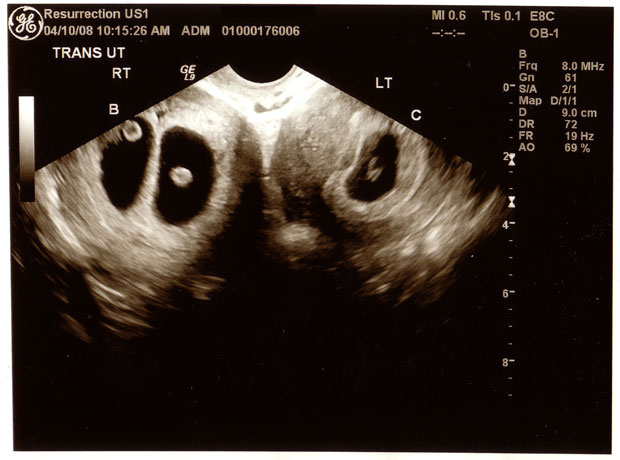

This is an ultrasound image belonging to friend of mine. It is not a joke; it is not a fake, and yes, of course I obtained her permission to post it here with the quite understandable proviso that I remove her name from it. Those of you who have seen these things before will note that she’s carrying triplets, but that’s not the crazy part. No, the real action here is that she’s split the three-baby load among her two uteruses.